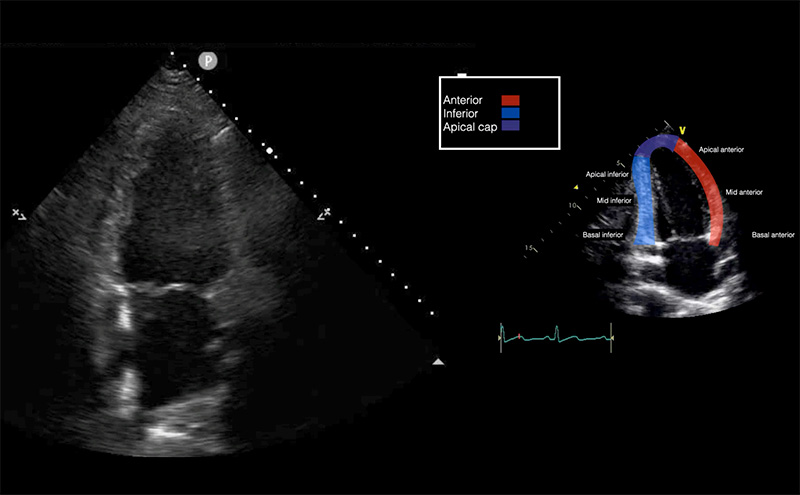

Emergency physicians should develop competency in the interrogation above segments using the parasternal long axis (PLAX), short axis (PSSX), and apical (four-chamber and two-chamber) views. We will be following cardiology convention with respect to screen orientation. PLAX can be obtained at the left 4th-5th parasternal space, with the probe marker towards the R shoulder. Rotating the probe 90º obtains the PSSX. The apical four chamber view is obtained at the point of maximal impulse, with the marker towards the patient’s left side. Rotating the probe 60º generates the apical two chamber view as demonstrated in Figure 1. This view is seldom used in EM practice but does allow for an alternate view of the anterior and inferior left ventricular walls.

Figure 1 - Apical 2-chamber view and corresponding anatomy

Apical Two Chamber (A2C)

Rotation of A4C 60º

Inferior and anterior LV